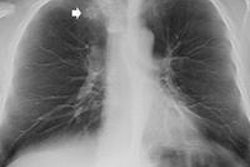

Low-dose digital tomosynthesis (DT) of the thorax administers a similar radiation dose to plain radiography but is far more accurate, can be applied to most lung nodule evaluations, and is useful for follow-up of the size change of nodules or other lesions, according to new prize-winning research.

DT is a form of limited-angle CT that allows reconstruction of multiple section images from a set of projection data acquired over a limited range of x-ray tube angles. It offers the potential for improved diagnostic performance over conventional radiography by substantially reducing the visual clutter of the overlying anatomy. Although it does not have the depth resolution of CT, DT provides high-resolution images in the coronal or sagittal plane with a substantial reduction in the radiation dose compared with CT, the authors explained.

Low-dose DT can show honeycomb fibrosis or dense pneumonic consolidation in patients with usual interstitial pneumonia (UIP). An air bronchogram is well noted in the consolidation of the right upper lobe. However, low-dose DT cannot demarcate the area of GGO in the basal lung because of poor contrast sensitivity, and it is hard to distinguish small nodular consolidation from thick fibrosis on low-dose DT, the researchers pointed out.